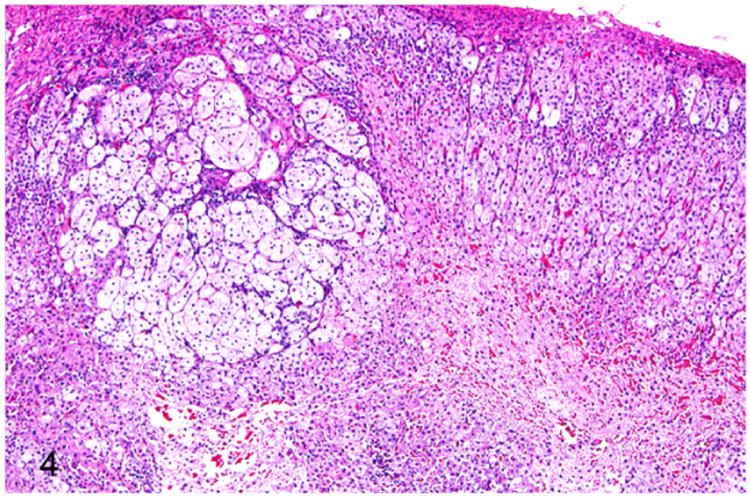

Adrenomegaly is not a prominent feature of adrenocortical hyperplasia.41 Histologically, the presence of multiple nodules is suggestive of nodular cortical hyperplasia. The hyperplastic nodules are well demarcated from the adjacent normal parenchyma. The adrenocortical cells within the hyperplastic nodules are well-differentiated and often contain numerous cytoplasmic vacuoles (Fig. 4). Mitotic figures are rarely seen in adrenocortical hyperplasia.41

Figure 4.

Proliferative lesions of the adrenal gland, ferret. Focal adrenocortical hyperplasia. The mass is formed by large clear cells with vacuolated cytoplasm. HE.